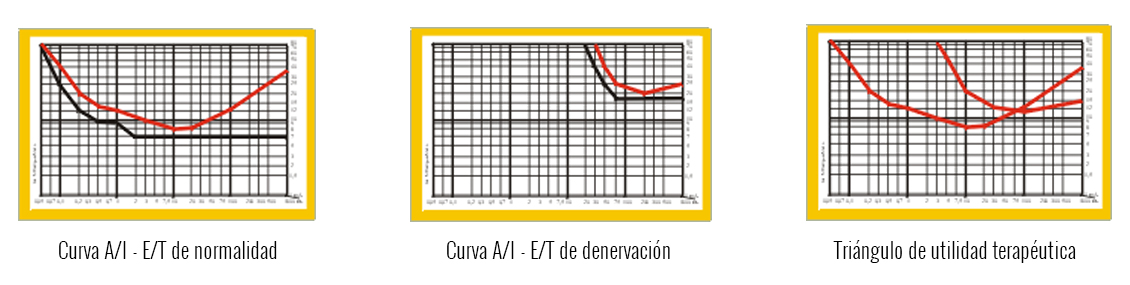

Las curvas de electroterapia son la forma visual de transcribir los datos obtenidos para realizar la terapia. La base de la electroterapia de respuesta motora y sensitiva de baja frecuencia la encontraremos en la réplica de diferentes parámetros de forma, tiempo e intensidades de pulsos, estos datos se ven reflejados en las denominadas curvas I/T – A/T. Las tres formas más características:Interpretación de las curvas A/I – E/T

Estas gráficas denominadas curvas son la representación de la respuesta nerviosa y muscular que se recoge en parámetros cuando se supera el umbral de excitación despolarizándose la membrana para desencadenar el potencial de acción. Con los gráficos que hemos mostrado anteriormente podemos entender ciertos comportamientos características a la hora de realizar la terapia de la electroterapia.- Por qué en un paciente no funciona una corriente siendo la excepción del resto de sus pacientes.

- Curvas de normalidad: Principalmente se centra en los datos recogidos para aplicar tratamientos con precisión a la hora de diseñas corrientes para fortalecimiento muscular, aumento muscular o mantenimiento de la masa muscular.

- Curvas de denervación: Sirve para precisar el grado de respuesta neuromuscular en una parálisis periférica y, de esta forma, poder establecer los parámetros para aplicar el tratamiento correspondiente.

- Triangulo de utilidad terapéutica: Este gráfico recoge los datos de la corriente a utilizar en caso de parálisis periféricas.